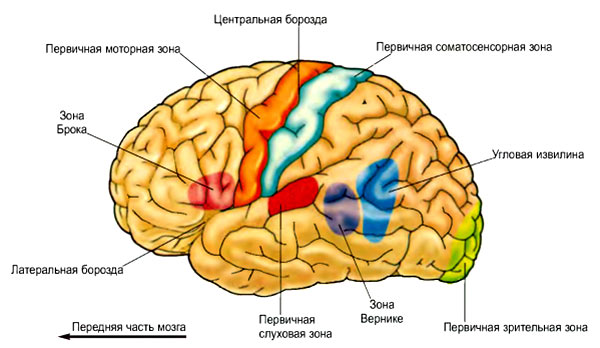

Схема чувствительных зон новой коры мозга